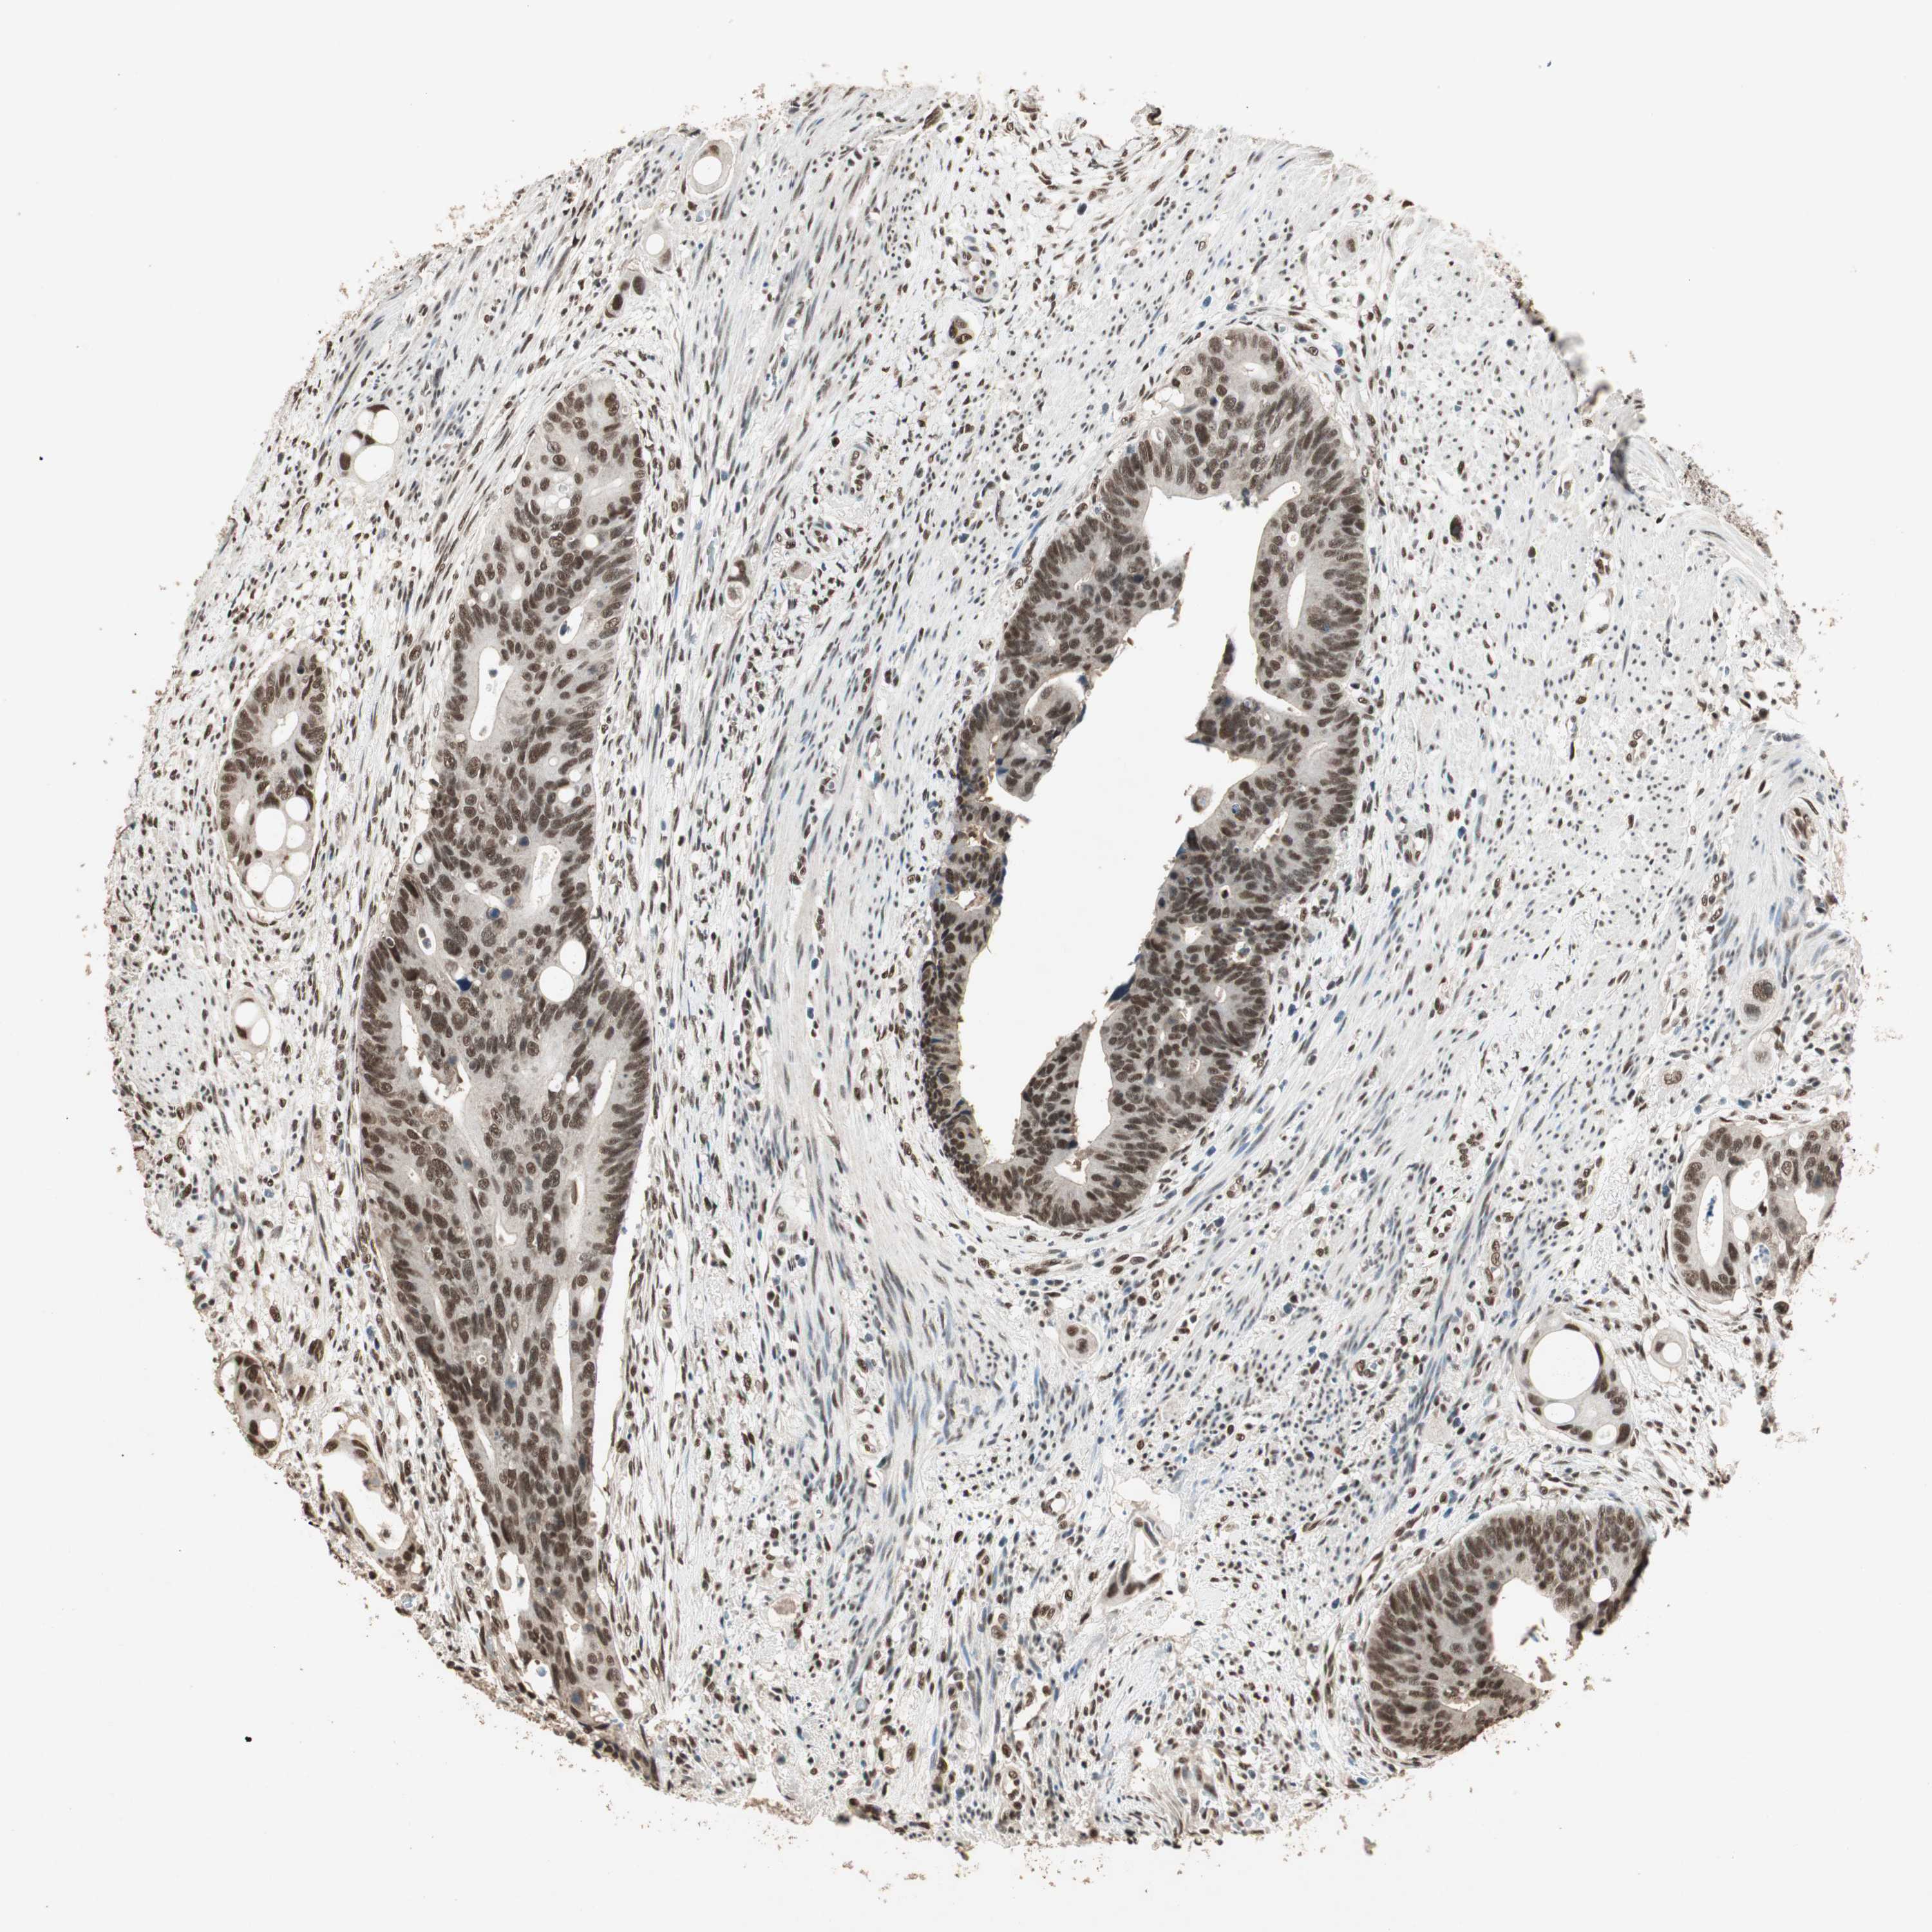

CANCER COLORECTAL CANCER Show tissue menu

Colorectal cancer

Colon adenocarcinoma